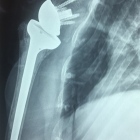

Estadísticamente las fracturas tanto del humero proximal ( hombro) como del radio distal (muñeca) son de alta incidencia en personas por arriba de los 55años, al igual que las lesiones tendinosas ( que suelen agudizar o completarse ) por arriba de esta edad....

Lo correcto es valorar radiograficamente y una adecuada exploración física dirigida por un especialista